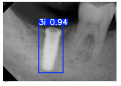

| Image Resolution = 825 × 1200 | ||||

|---|---|---|---|---|

| Test Image 1–4 | ![]() | ![]() | ![]() | ![]() |

| Accuracy | 94.13% | 95.29% | 92.88% | 91.80% |

| Recall | 96.71% | 94.03% | 93.88% | 92.15% |

| Model reference time | 6.57 ms | 7.08 ms | 7.12 ms | 6.43 ms |

| Dentists’ average diagnostic time | 2.78 s | 4.55 s | 7.78 s | 7.23 s |